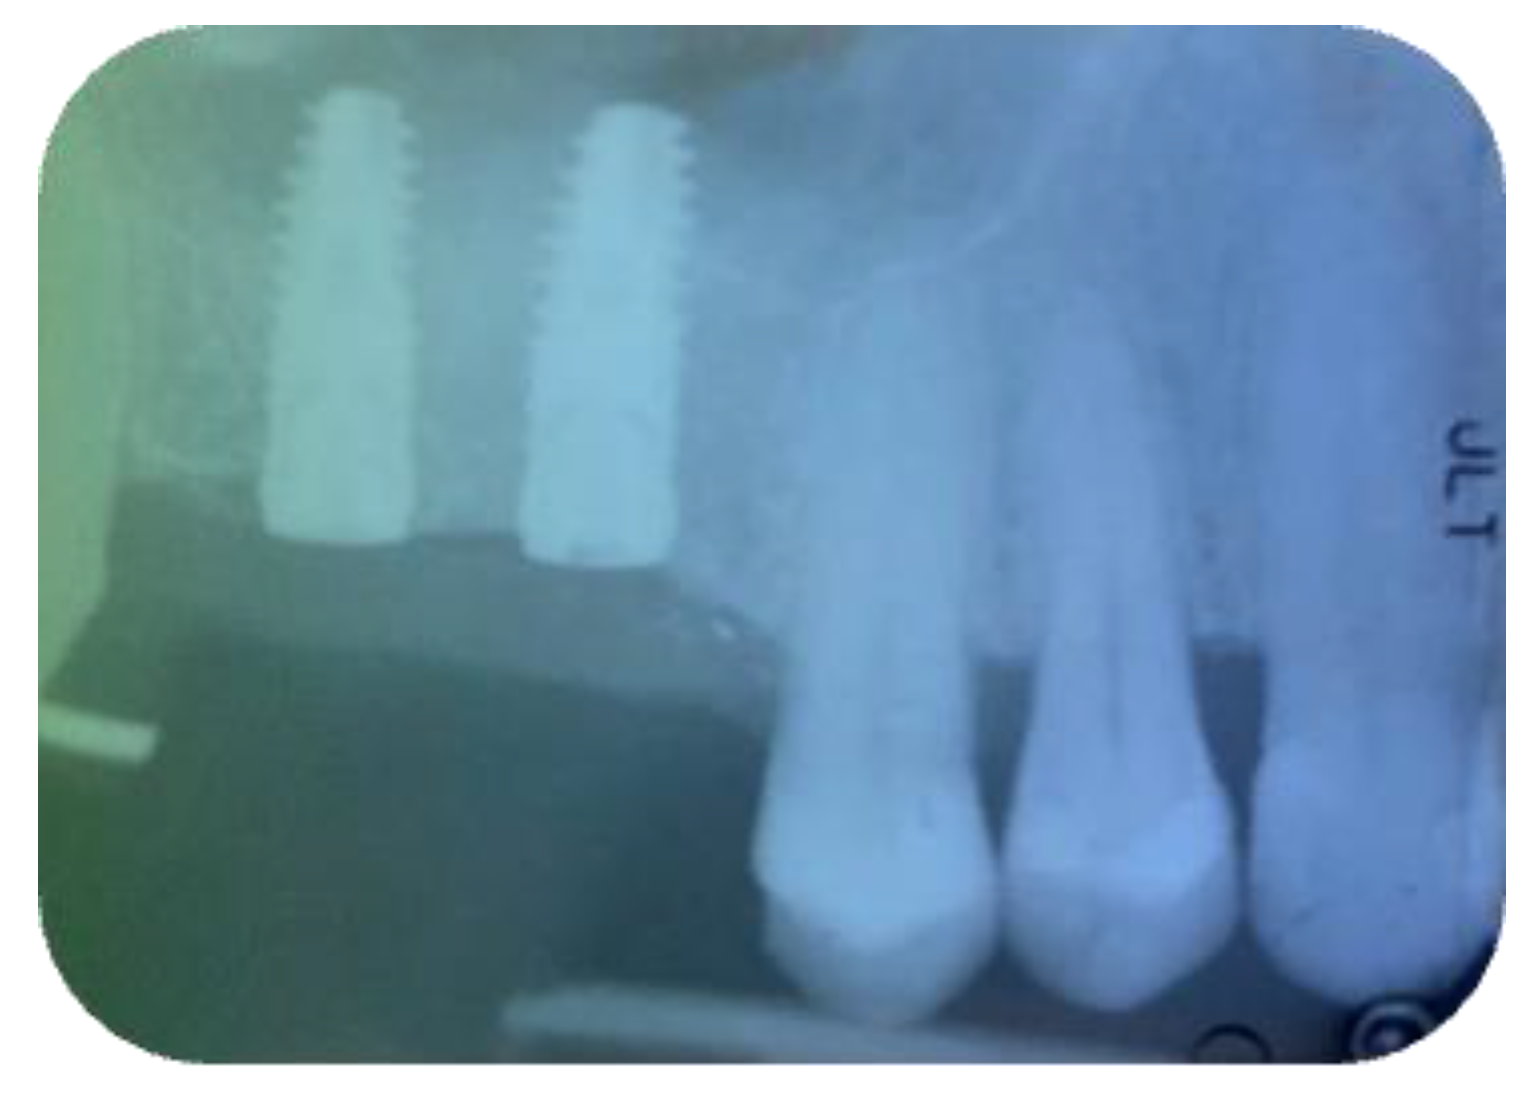

2.1. Surgical Procedures

2.2. Follow-Up